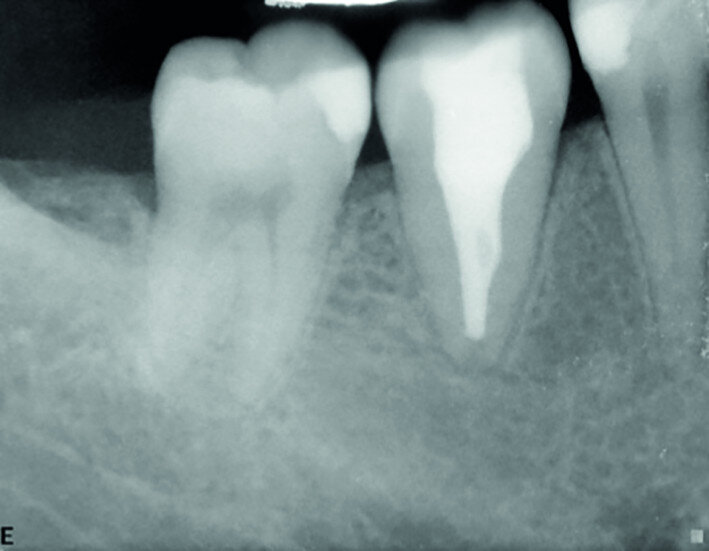

Fig. 19a: Radiographs: Pre-op periapical.

Fig. 19b: Radiographs: Immediately after transplantation.

Fig. 19c: Radiographs: One-year recall.

Fig. 19d: Radiographs: Two-year recall.

A 16-year-old female patient required extraction of a maxillary molar. Tooth #18 was transplanted to site #16. Root development was still continuing after two years (Figs. 19a–d).